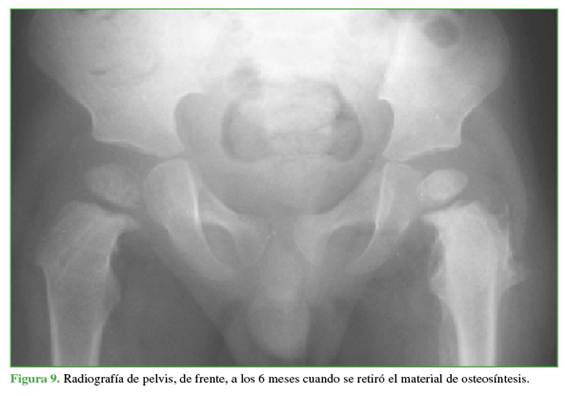

En las Figuras 9 y 10, se muestra la resolución a los 6 y 24 meses del retiro del material.